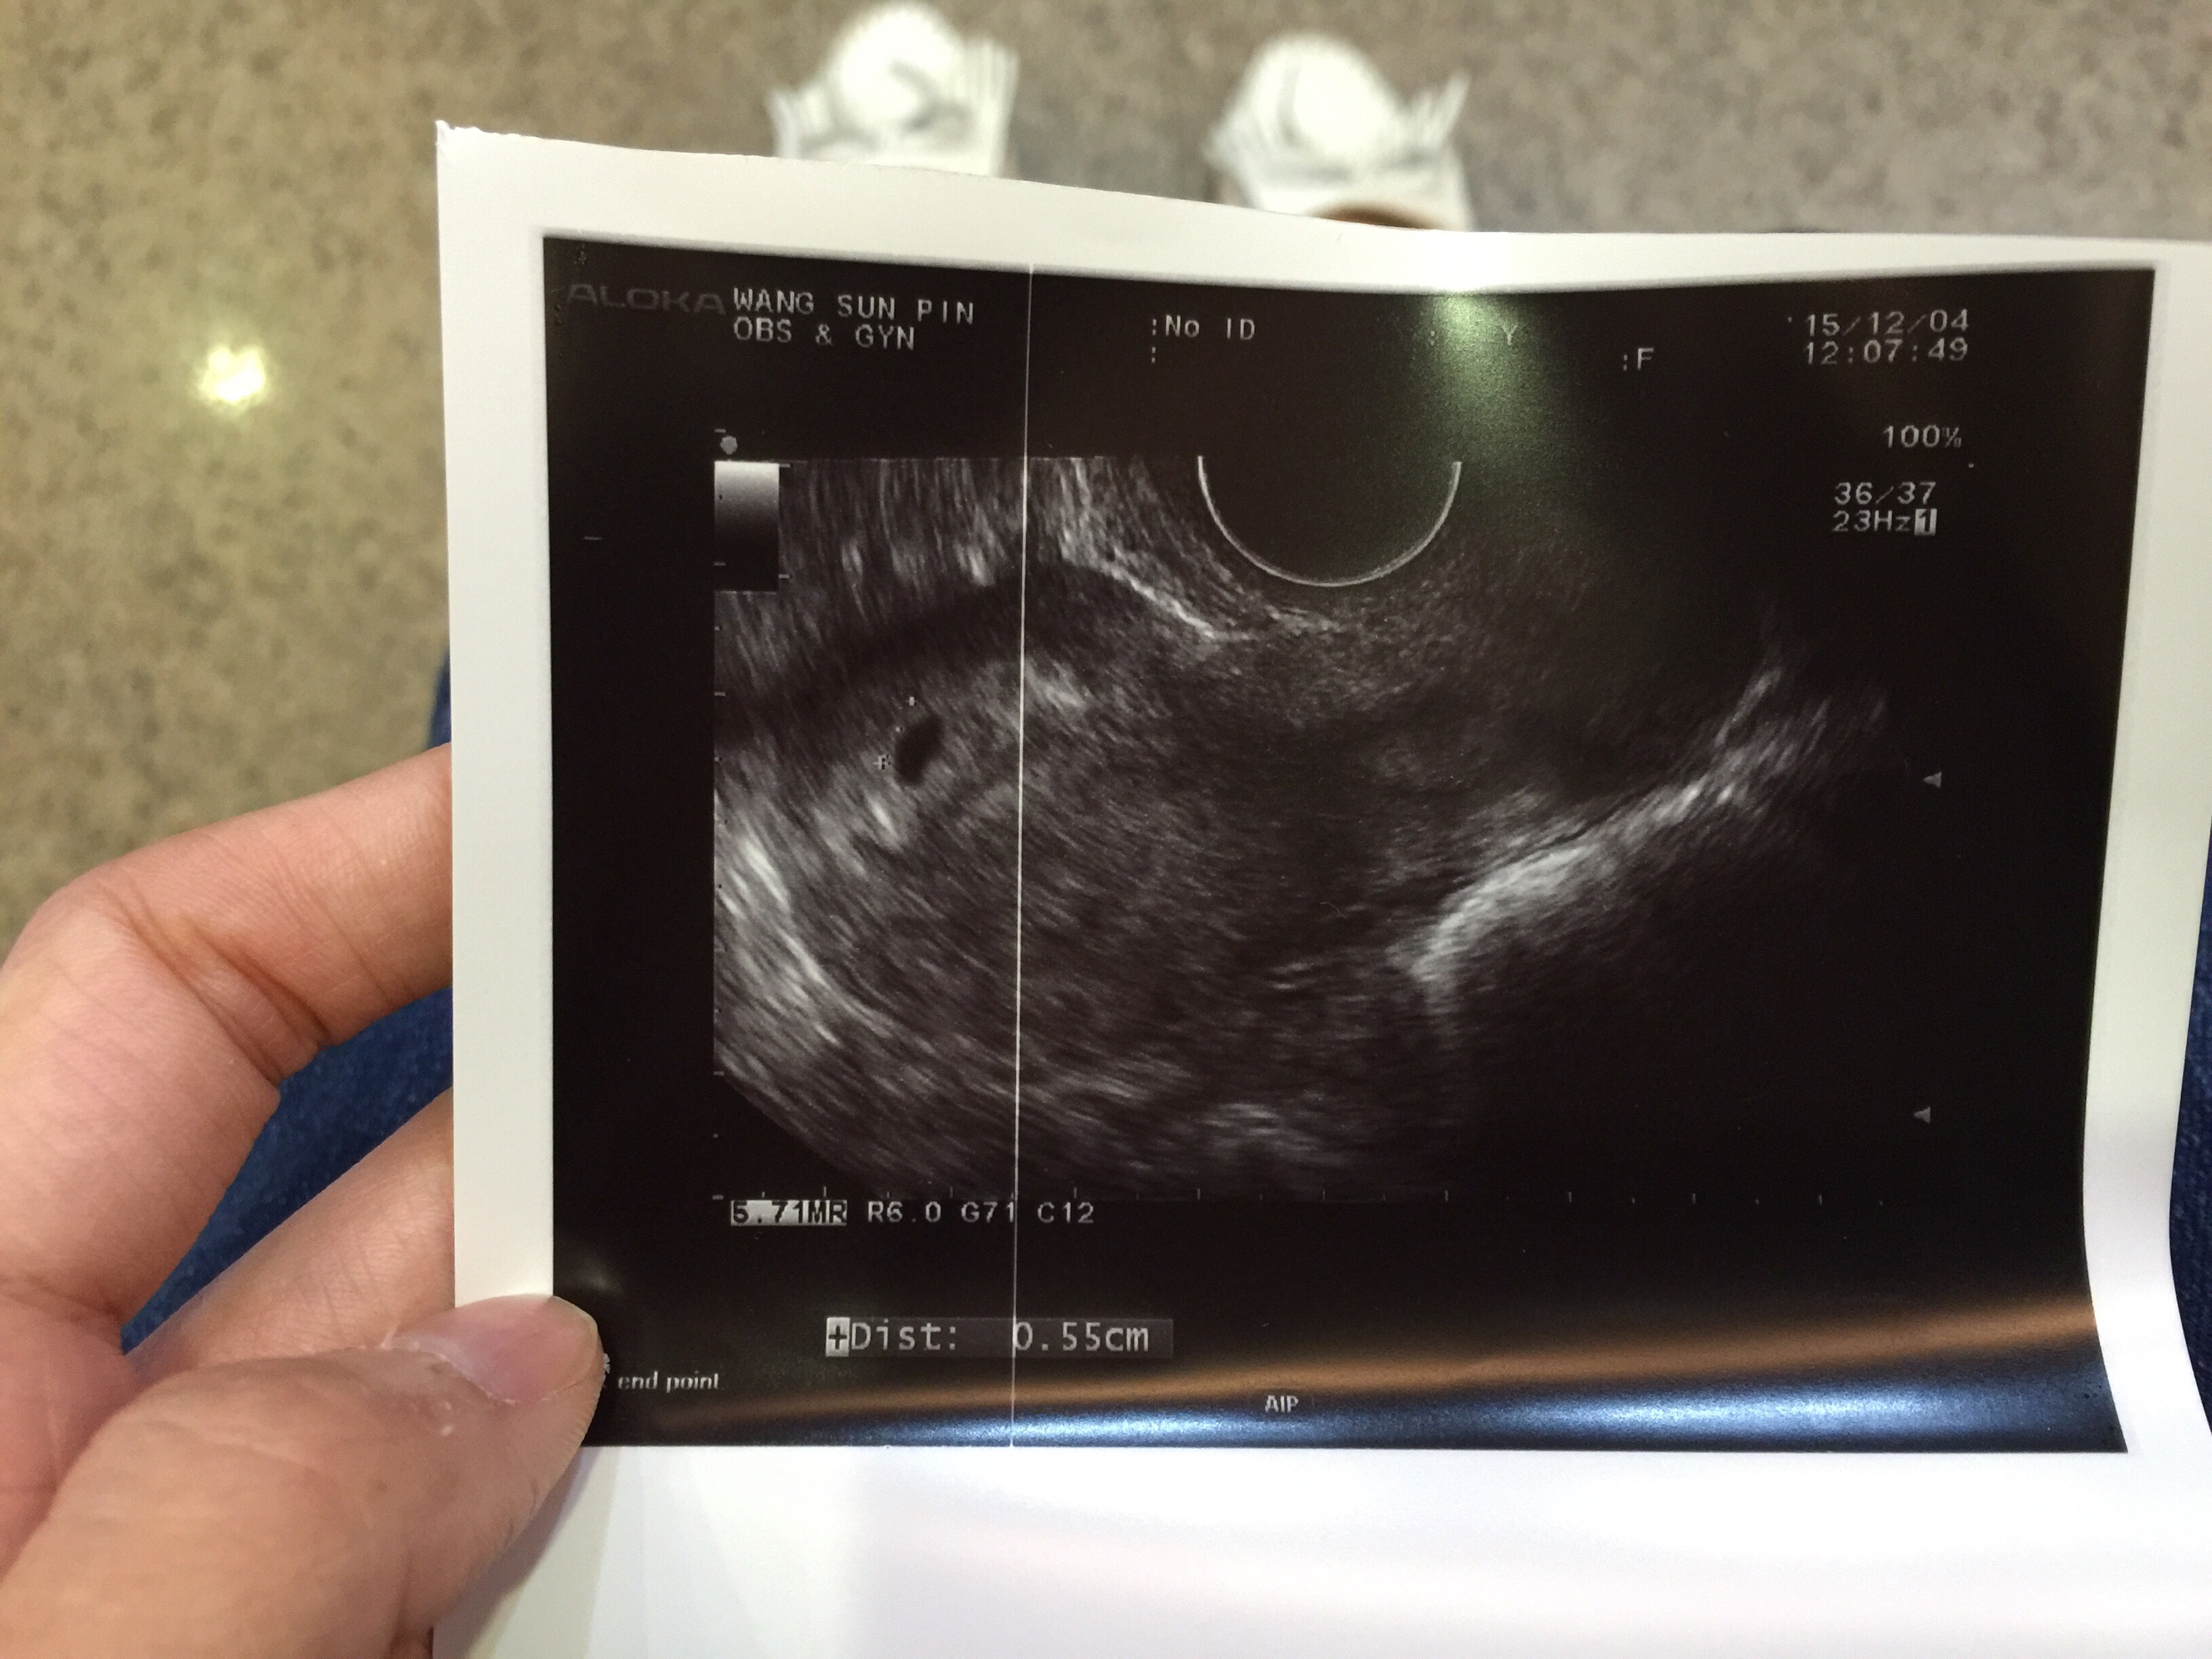

回診後陰超腹超都照不到,我也覺得很正常才高溫9天而已!!

5W0D一樣腹超照不到..請他照陰超,竟然說你想照就照吧= =

照完之後說,就跟你說照不到,請我驗尿說有變深應該在長大

朋友當天建議我換間婦產科,換了C醫生之後有找到疑似的點點!

因為設備比較好的樣子,C醫生用放大的倍數找說非常的小不能確定

以月經週期算起來已經5W4D了..不知道今晚照不照得到...